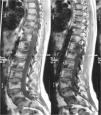

Osteomesopicnosis: aportación de tres casos

E. de la Hoz Adamea, B. Domínguez Fuentesa, D. García Gila, P. Moise Cosanob

a Servicio de Medicina Interna. Hospital Universitario de Puerto Real. Cádiz

b Servicio de Radiodiagnóstico. Hospital Universitario de Puerto Real. Cádiz